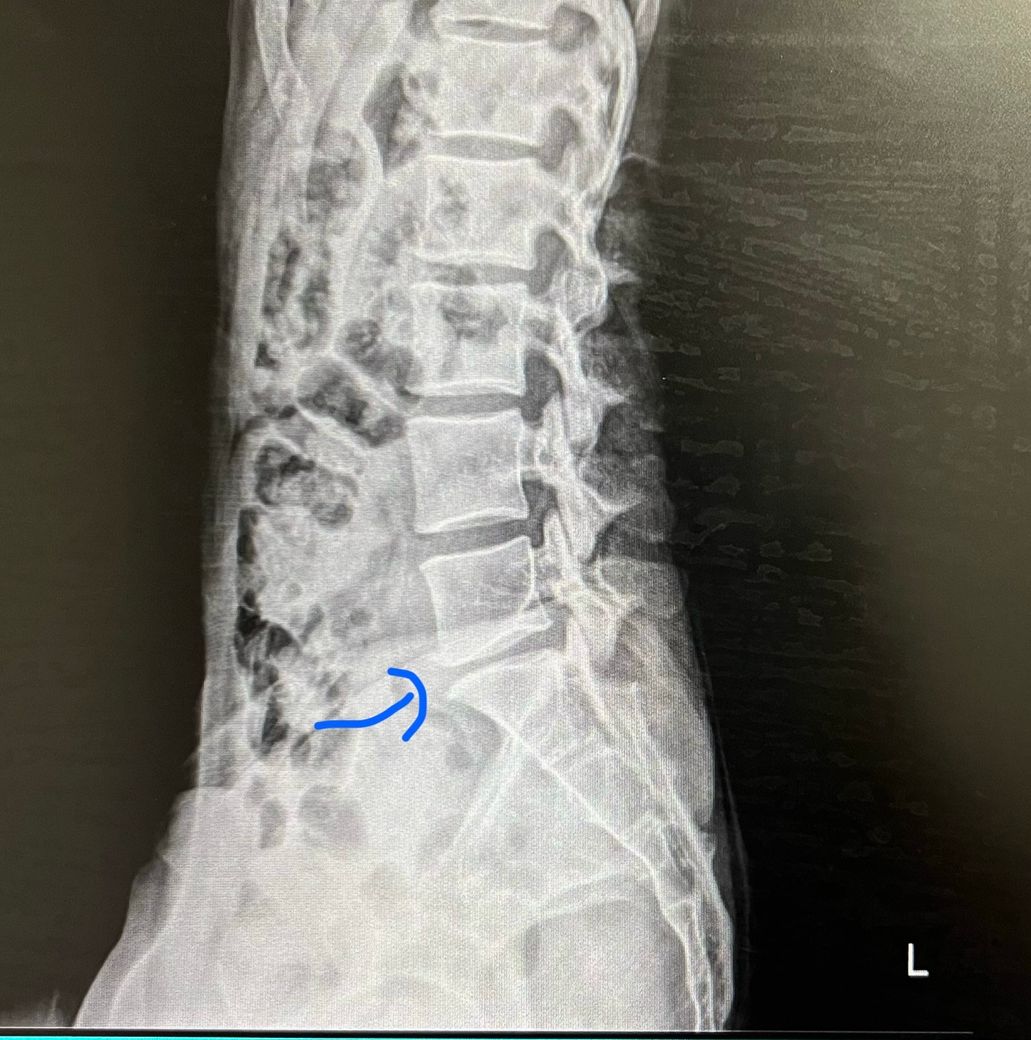

몇주전부터 방사통 재발해서 엑스레이 찍어봤더니

꼬리뼈에 가까운 5,6번? 뼈 간격이 3분의2정도 좁아졌습니다

최근 엑스레이 사진 첨부합니다

• 1번 째 사진